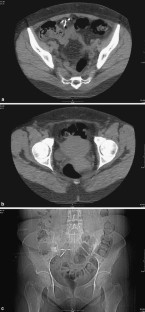

Fig. 1